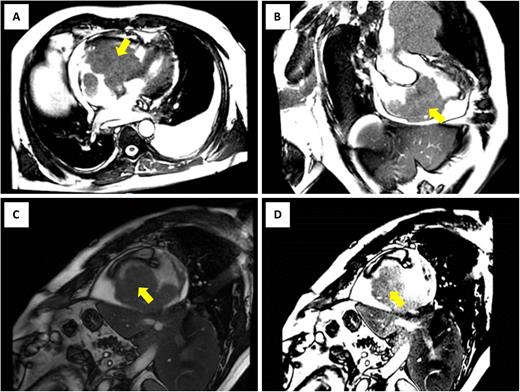

Chronic lymphocytic leukemia (CLL) is the most common hematological malignancy in the USA. (American Cancer Society, 2022) It is more prevalent in elderly males and commonly presents with a relatively benign course. Extra-medullary disease is very rare and is not well characterized. Skin and CNS involvement were reported to be the most common but other organs can also be involved. (Ratterman et al., 2014) We report a 51-year-old male patient with a past medical history of mutation negative CLL in remission, who presented with fatigue, dyspnea on exertion, night sweats and a neck mass. The physical examination revealed an enlarged non-tender left supraclavicular lymph node measuring 5-6 cm in diameter but was otherwise unremarkable. Laboratory investigations were notable for leukopenia and thrombocytopenia. Due to high suspicion for an underlying malignant process, a full body computerized tomography (CT) scan was obtained and showed an 8.8 cm soft tissue mass-like lesion occupying the majority of the right atrium and extending into the right ventricle, with probable pericardial involvement. Enlarged left supraclavicular and mediastinal lymph nodes were also present and had a mild mass effect on the traversing left internal thoracic artery and left pulmonary artery. A transesophageal echocardiogram and cardiac magnetic resonance imaging (MRI) (Figure 1) were done to better characterize the cardiac mass. They confirmed a large infiltrating mass (measuring 10 x 7.4 cm) in the right atrium and ventricle, extending into the inferior vena cava inferiorly and coronary sinus posteriorly. A bone marrow biopsy showed normocellular marrow with no infiltration. Left supraclavicular excisional lymph node biopsy was performed and histopathology was consistent with Small Lymphocytic Lymphoma (SLL)/CLL with increased proliferation index (up to 40% by KI-67 immunohistochemical stain) and normal karyotype. This confirmed extramedullary SLL/CLL relapse with lymphadenopathy and cardiac mass. The patient was started on chemo-immunotherapy with Obinutuzumab-Venetoclax with marked improvement in B symptoms and dyspnea. Cardiac infiltration by CLL B-cells has been shown on autopsies of CLL patients. (Schwartz et al., 1981) In practice, clinically significant cardiac or pericardial involvement by SLL/CLL is extremely rare with only a few case reports in literature. (Posch et al., 2021) (Nnaoma et al., 2019) (Goncalves et al., 2002) Extramedullary CLL disease suggests a more aggressive disease and warrants a high level of suspicion for diagnosis. (Ratterman et al., 2014)